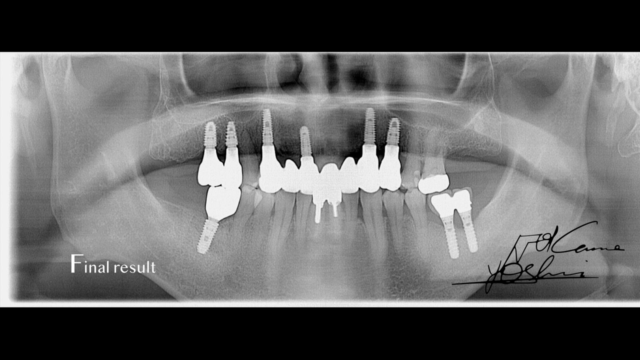

CTパノラマ画像(AFTER)です。